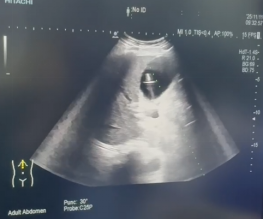

1. 精准导航,一步到位:术前,通过磁共振胆管水成像(MRCP)精确绘制胆道“地图”,清晰显示梗阻部位与胆囊关系。术中,在超声实时引导下,采用经典的 Seldinger技术,犹如“穿针引线”,将穿刺针精准送入胆囊。值得一提的是,术中我们严格遵循安全路径,即经肝的右下周边穿刺,经胆囊床进入胆囊,此举有效避免了针道经过肝门等重要结构,相关并发症风险得以显著降低。 随后置入导丝、扩张通道、留置引流管,一步到位。

术中在超声实时引导下进 通过Seldinger技术建立胆囊、胆总管

行胆囊精准穿刺 至十二指肠的手术通道